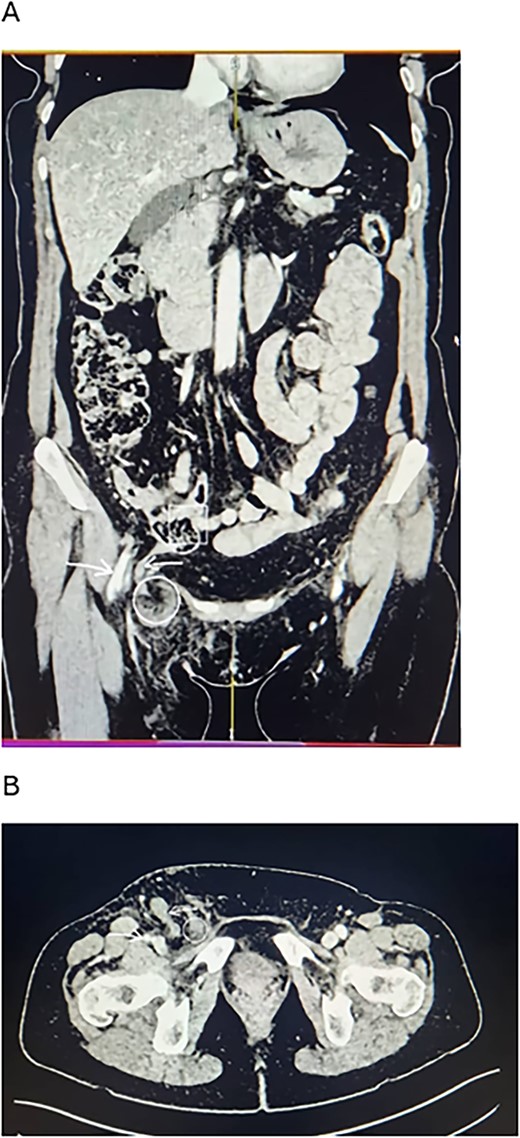

With a clinical suspicion of incarcerated femoral hernia, we requested an urgent CT scan, which showed incarcerated femoral hernia containing fluid, fat, and distal half of the appendix (Fig. 1).

CT scan findings of the patient. (A) Coronal view. (B) Axial view. Note the long appendix (reverse arrow) extending from the ileocecal junction (squared area) into the femoral sac (circled area). There is stranding around the sac in the femoral canal. The femoral vessels (forward arrow) run beside the canal.